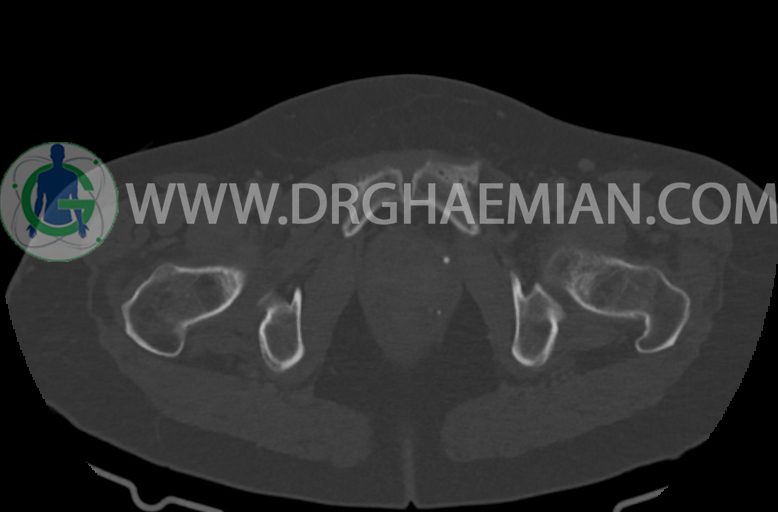

–ساختار Cystic multiseptate همراه با Enhancing thick septation به ابعاد 79x62mm در

لگن دیده می شود که در درجه اول مطرح کننده ی ضایعات نئوپلاستیک تخمدانی نظیر mucinous cyst adenocarcinoma است.

–شواهد هیسترکتومی